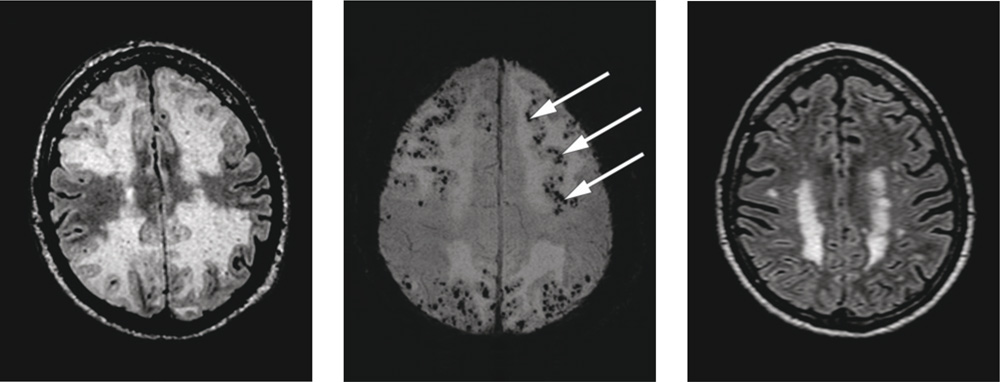

MR caput ble utført etter reinnleggelsen. FLAIR-bilder viste utbredt ødem i begge storehjernehemisfærer (bildet til venstre). Suseptibilitetsvektede MR-bilder (SWI), spesielt følsomme for blodprodukter, viste tallrike mikroblødninger i affiserte områder (bildet i midten). Mikroblødningene ble tolket som cerebral amyloid angiopati. Det ble tatt EEG, som viste langsom epileptiform aktivitet. Temporalisbiopsi var positiv. Sett i sammenheng med sykehistorien passet bildefunnene best med cerebral amyloid angiopati av inflammatorisk type. Det ble igangsatt behandling med prednisolon, med god effekt. Senere ble det gitt metotreksat og antiepileptisk behandling med Orfiril.

MR-kontroll etter seks uker viste tilbakegang av ødemet i hjerneparenkymet (bildet til høyre). Pasienten var da betydelig bedre, dog ikke helt restituert.